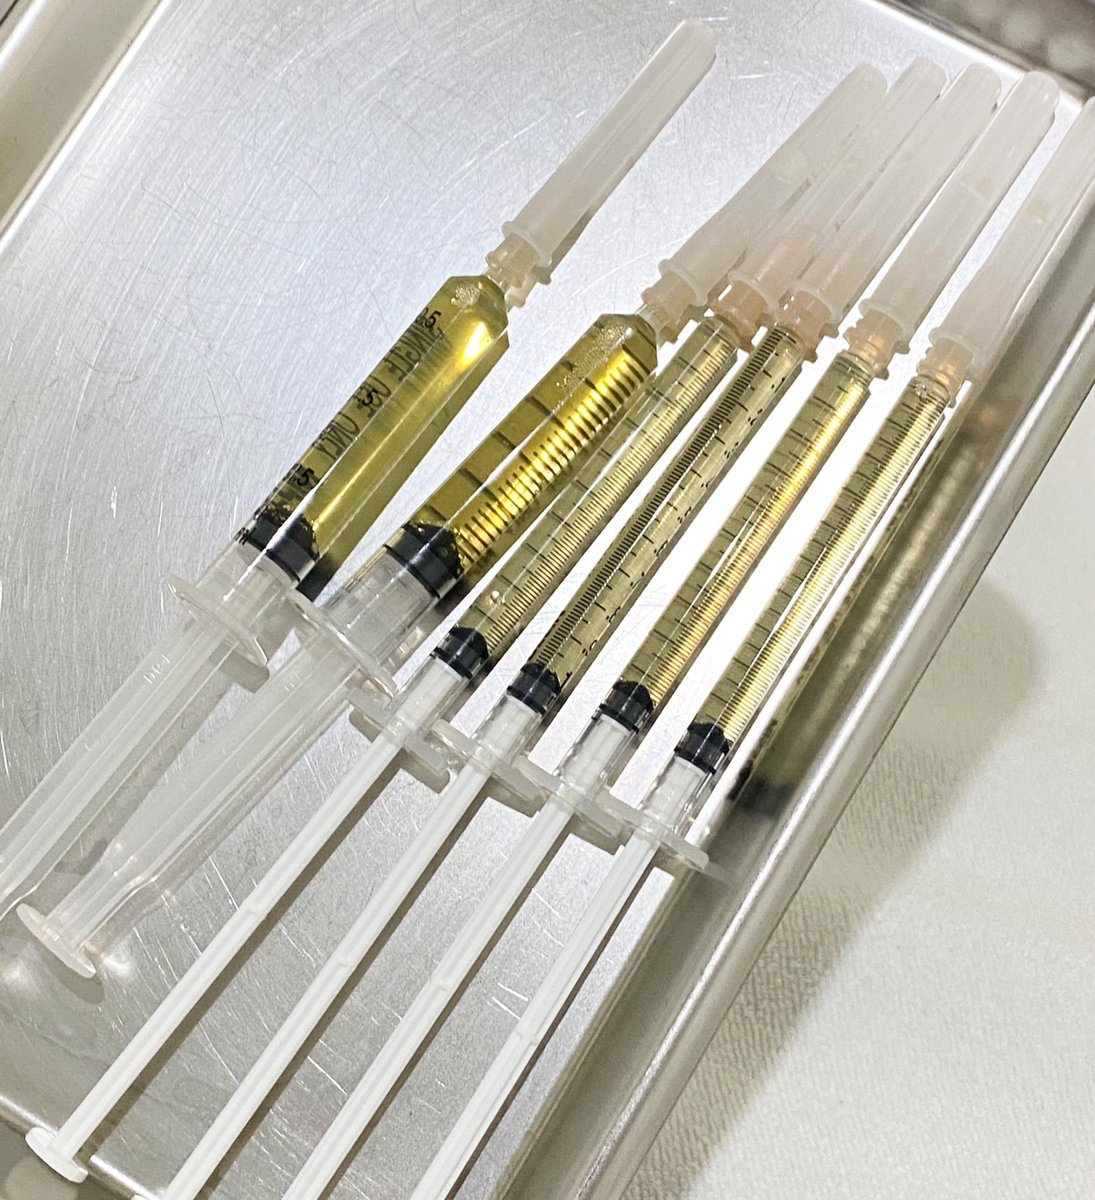

I’m shocked that the 2 PRP injections that this patient got last year did not help. /s I wonder if the Doctor that prescribed and injected them and charged cash for them feels like they did the right thing medically.

ทำ PRP มา ครบ15วัน เดี๋ยวมารีวิวเลย คือมันโครตดี โครตปัง ดีกว่าฉีดมาเด้หลายเท่า แล้วมันเป็นเลือดเราเองไง ไม่แพ้ที่เปลี่ยนมาฉีดprp เพราะเคยแพ้มาเด้ที่นึง เจอprp ไปทั้งใต้ตา ทั้งผิวหน้า ปริ่ม เดี๋ยวขอรวบรวมมาทำรีวิว

ดองรีวิวไว้นานมาก วันนี้ได้คิวของ prp ใต้ตาที่สรรหาไปทำมาบ้าง!!! ต้องเล่าก่อนว่า prp มันคือการปั่นเลือดเอา พลาสม่าของเราไปฉีดหน้าให้ฉ่ำ กระตุ้น ฟื้นฟูอะไรแบบนี้ มันสามารถฉีดได้ทั้งหน้าเลยไม่ใช่แค่ใต้ตา ขึ้นอยู่กับว่าเราได้เลือดมากน้อยแค่ไหน ปั่นมาแล้วเหลือเท่าไหร่อะไรแบบนี้